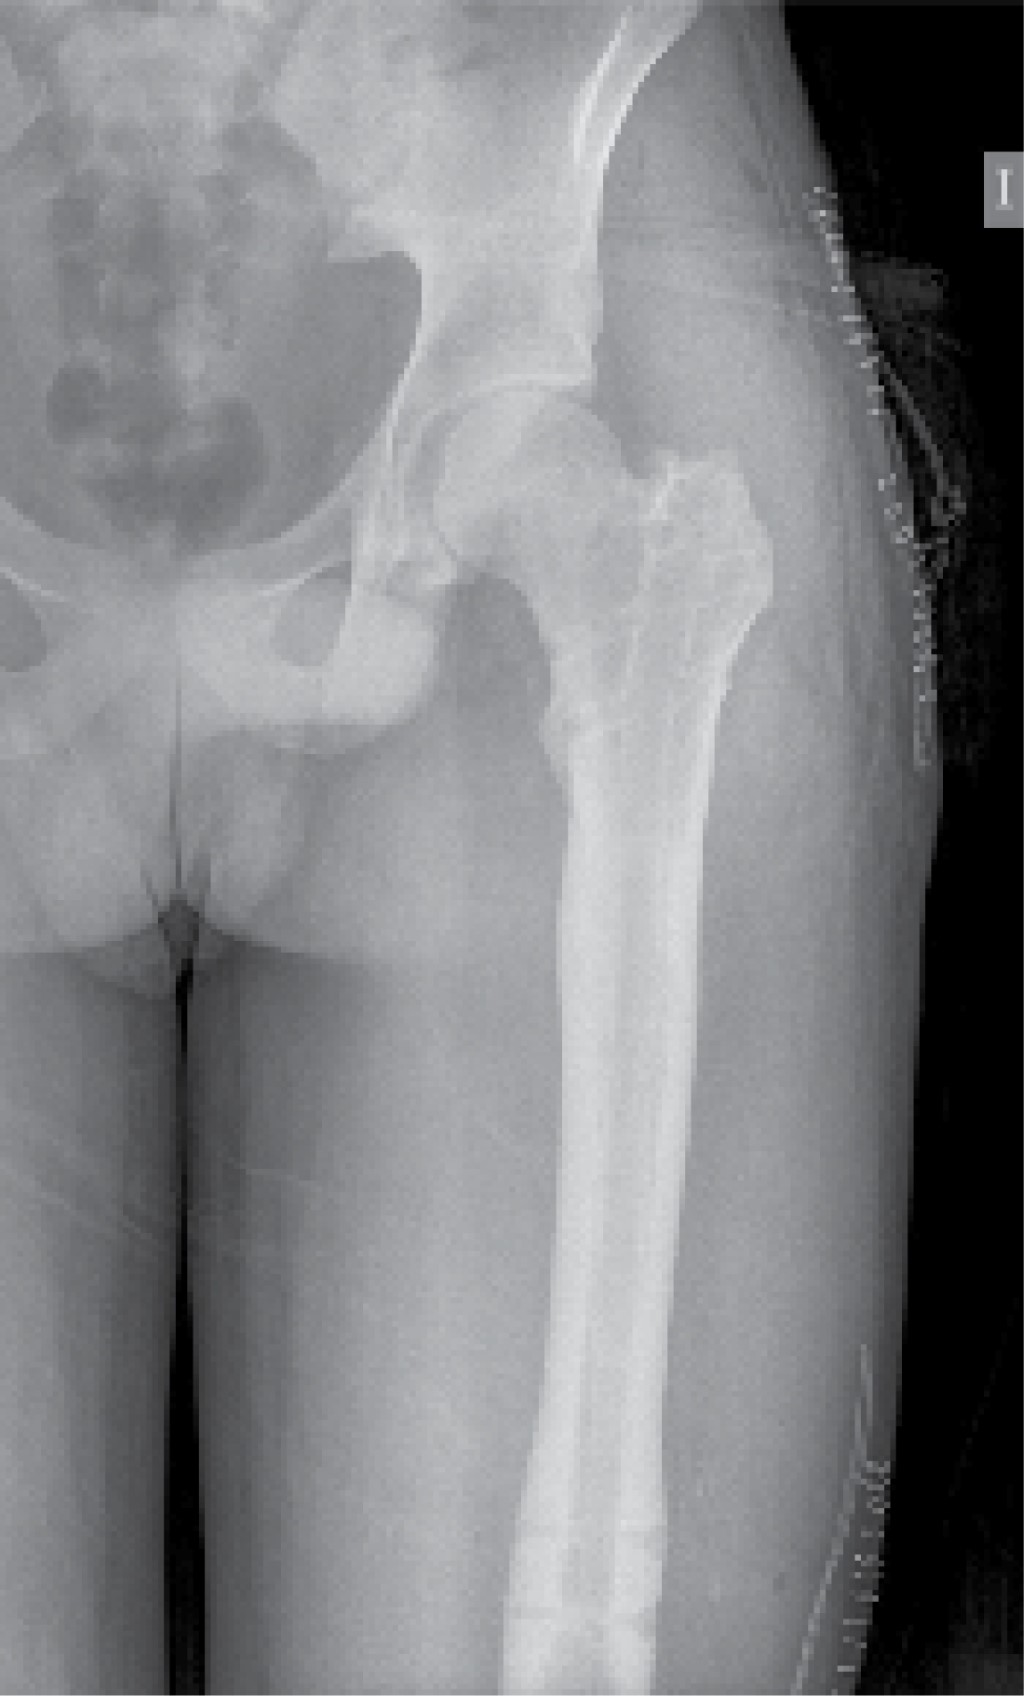

Se identificó el lugar de la osteotomía femoral siguiendo el método habitual descrito por Paley y colaboradores,13 realizándose mediante múltiples perforaciones a través de un abordaje lateral. Como describen algunos autores, estas perforaciones registran una baja tasa de tromboembolismo pulmonar.2 El punto de entrada del clavo se realizó en la punta del trocánter mayor a través de un abordaje lateral proximal (Figura 1), que permitió el fresado del canal femoral hasta 1.5-2 mm mayor que el diámetro definitivo del clavo seleccionado. Se introdujo el clavo intramedular Precice® hasta el borde proximal de la zona de osteotomía y se completó la misma a través del abordaje lateral, introduciendo el clavo hasta su localización definitiva y bloqueándolo proximal y distalmente (Figura 2). Por último, se realizó la distracción del clavo 1-2 mm para asegurar el correcto funcionamiento del dispositivo magnético.

Figura 1